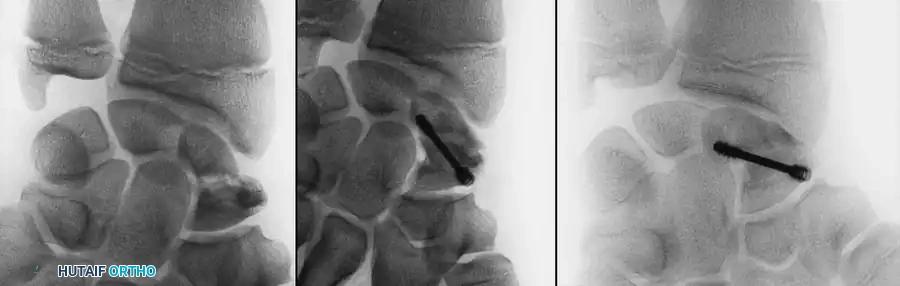

Image

These injuries are highly unstable. If the intraarticular component is displaced and large enough to accept fixation, ORIF is indicated.

The approach is typically dorsal, splitting or elevating the extensor mechanism. The articular surface is anatomically reduced under direct vision and secured with transverse smooth K-wires or, in older adolescents, miniature headless compression screws.